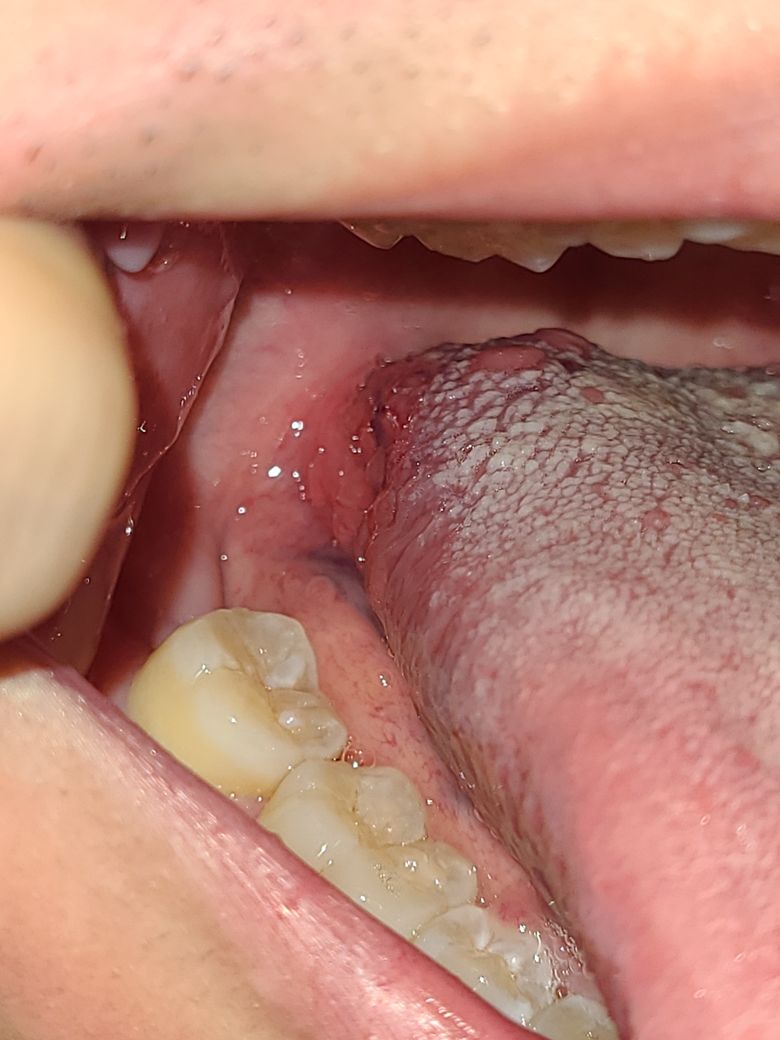

입안에 종양 같은게 있는데 뭘까요??

얼마전에 혀클리너를 너무 강하게 사용해서 상처가 난 거 같기도 한데 큰 병은 아닌지 걱정되네요

사진에 보이는 것은 혀의 옆면에 위치한 부분으로, 혀 클리너 사용으로 인해 발생한 자극으로 보일 수 있습니다. 이런 종류의 자극이나 손상은 때때로 부기, 발적 또는 작은 궤양의 형태로 나타날 수 있으며, 대부분은 시간이 지나면 자연스럽게 치유됩니다.

그러나, 이 부위가 지속적으로 아프거나 크기가 커지거나 다른 증상이 동반되는 경우는 이비인후과 나 구강안면외과의 진료를 받으시기 바랍니다.